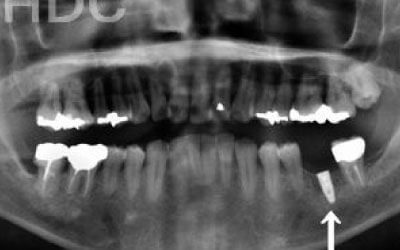

骨が薄い場合、そのままインプラントを行うのはお勧めできません。

ただし、事前に骨を増やす治療を行ったり、インプラントと同時に骨を増やす治療をすることで、インプラントは可能です。

前歯はもともと骨が薄く、歯が抜けると時間の経過とともにさらに骨が痩せてきてしまうので、インプラント治療の難易度が高い場所です。

ただ結論からお話すると、インプラント治療は可能です。

なぜなら、もし仮に骨が薄くても、骨の治療によって厚みが増せば、安全にインプラント治療が行えるからです。

1)インプラント治療を行う前に、骨の治療が必要かもしれません。

4)骨の状況をしっかり把握するためにも、CT撮影が必須となります。